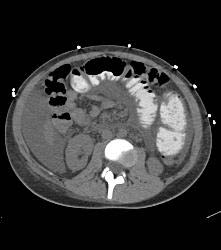

B-cell Lymphoma in Ileum